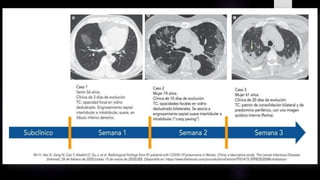

 Durante los días 0 – 2, lo predominante fue una TC normal en algo más de la mitad de los

casos y en un 44% de pacientes se encontró opacidad en vidrio esmerilado, generalmente

unilateral.

 Posteriormente, a los días 3 – 5, el hallazgo predominante fue opacidad en vidrio

esmerilado en un 88% de los pacientes seguido por consolidaciones, la afectación fue en

un 30% multilobar.

 A los días 6 -12, el hallazgo predominante fue opacidad en vidrio esmerilado con un

aumento en la frecuencia de consolidaciones, la afectación multilobar llegó al 50%.

H. Shi, X. Han, N. Jiang y colaboradores Fuente: The Lancet Infectious Diseases Feb 24, 2020 Radiological

findings from 81 patients with COVID-19 pneumonia in Wuhan, China: a descriptive study